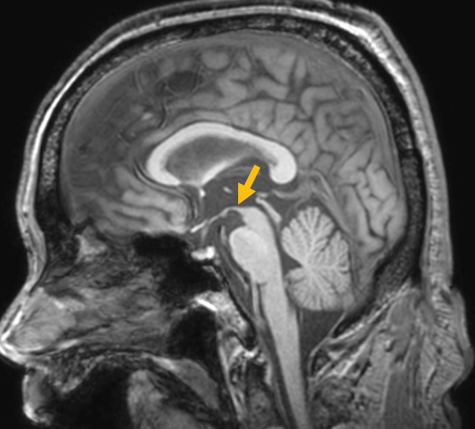

진행 핵상 마비는 대표적인 파킨슨 증후군 중의 하나입니다. 파킨슨병과 다른 점은 질병의 초기부터 중심을 잡기 어려운 체위 불안정이 나타나 자주 넘어진다는 것입니다. 파킨슨병의 경우 질병이 상당히 진행된 뒤에 체위 불안정이 나타납니다. 또한 진행 핵상 마비에서는 목 주위 근육을 비롯한 몸 중심 근육의 경축이 나타나, 목을 뒤로 젖히면서 걷는 모습이 보입니다. 그리고 눈의 운동을 조절하는 기능에 장애가 나타나 아래쪽을 바라보는 데 문제가 생겨 계단을 내려갈 때 어려움을 겪는 경우가 많습니다. 진행 핵상 마비가 의심되는 경우, 뇌 자기공명영상(MRI)에서 중뇌의 위축이 비정상적으로 심하게 나타나는 소견을 확인하거나, 뇌포도당 양전자 단층촬영(PET)에서 전두엽과 중뇌의 대사 기능이 저하된 소견을 확인하여 진단에 참고할 수 있습니다.

[진행핵상마비 환자의 뇌자기공명영상에서 확인되는 중뇌 위축 소견]